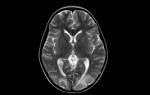

- МРТ – этот метод обладает высокой точностью, достигающей 99%. МРТ позволяет оценить изменения в паутинной оболочке, определить местоположение кисты и исключить другие заболевания с похожими симптомами, такие как опухоли и абсцессы.

Как МРТ покажет арахноидит головного мозга?

Слипчивый арахноидит характеризуется слипанием нервных корешков и спинного мозга, которые могут выглядеть как слипшиеся пучки на МРТ-снимках. Этот признак лучше всего виден на Т2-взвешенных изображениях. Повышенный сигнал от окружающих тканей на Т2-взвешенных изображениях указывает на отек и воспаление.